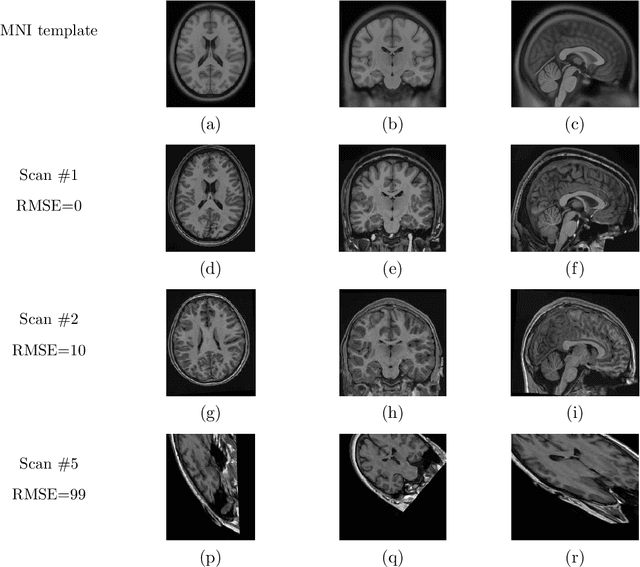

Abstract:Registration of one or several brain image(s) onto a common reference space defined by a template is a necessary prerequisite for many image processing tasks, such as brain structure segmentation or functional MRI study. Manual assessment of registration quality is a tedious and time-consuming task, especially when a large amount of data is involved. An automated and reliable quality control (QC) is thus mandatory. Moreover, the computation time of the QC must be also compatible with the processing of massive datasets. Therefore, deep neural network approaches appear as a method of choice to automatically assess registration quality. In the current study, a compact 3D CNN, referred to as RegQCNET, is introduced to quantitatively predict the amplitude of a registration mismatch between the registered image and the reference template. This quantitative estimation of registration error is expressed using metric unit system. Therefore, a meaningful task-specific threshold can be manually or automatically defined in order to distinguish usable and non-usable images. The robustness of the proposed RegQCNET is first analyzed on lifespan brain images undergoing various simulated spatial transformations and intensity variations between training and testing. Secondly, the potential of RegQCNET to classify images as usable or non-usable is evaluated using both manual and automatic thresholds. The latters were estimated using several computer-assisted classification models through cross-validation. To this end we used expert's visual quality control estimated on a lifespan cohort of 3953 brains. Finally, the RegQCNET accuracy is compared to usual image features such as image correlation coefficient and mutual information. Results show that the proposed deep learning QC is robust, fast and accurate to estimate registration error in processing pipeline.